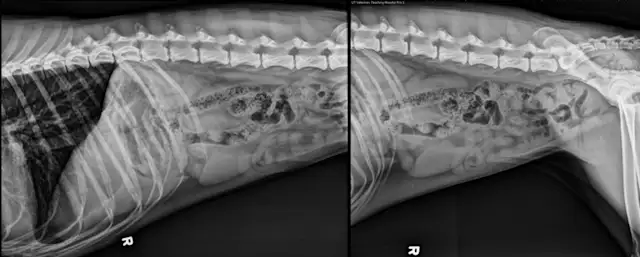

Right lateral abdominal x-ray of dog.

FIGURE 1: Lateral Abdominal View

The lateral abdominal view includes the entire diaphragm cranially and the greater trochanter caudally. Position the cranial edge of the collimator light 2 to 3 fingerbreadths cranial to the xiphoid process. Align the caudal edge of the light at the level of the greater trochanter. Center the beam over the caudal aspect of the 13th rib.1 Using soft ropes or tape, pull the thoracic limbs cranially and pelvic limbs caudally. Pulling the hind limbs caudally will help eliminate superimposition of the femoral muscles over the caudal portion of the abdomen.1  Collimate to include the patient’s dorsal and ventral borders in the radiograph.